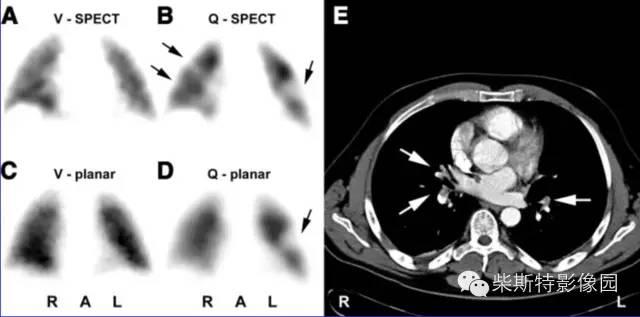

V/Q-SPECT(肺通气/灌注-单光子发射计算机断层成像技术)

V/Q-SPECT显像诊断PE的标准:与平面V/Q显像一样,检测到肺通气与肺灌注不匹配。

coronal-冠状位 sagittal-矢状位 transverse-横断位

几个典型肺栓塞患者的V/Q-SPECT显像:肺通气/灌注不匹配(箭头所指为灌注缺损)

V/Q-SPECT-CT融合显像技术

双肺多发栓塞,节段性V/Q不匹配(SPECT断层现象:A、B),(平面显像:C、D),CTPA:栓子位于右肺中动脉分支和双侧下肺动脉分支

患者患有COPD和肺气肿,右肺上叶肺大疱导致V/Q显像不匹配(假阳性),肺通气分布不均在COPD患者中较常见,箭头所指为灌注缺损。